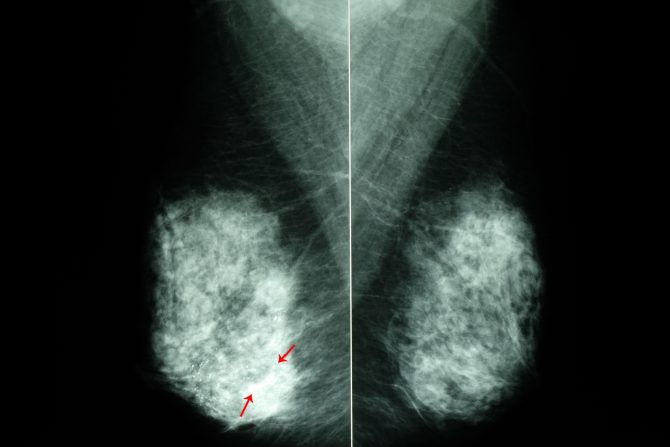

Kalcifikati u dojci su male naslage kalcijuma koje nastaju u tkivu dojke. Ovo su česte promene, uglavnom se javljaju posle 50. godine života i u velikoj većini slučajeva dobroćudne su prirode. Kalcifikati u dojci nisu praćeni simptomima i mogu se otkriti samo posle mamografskog snimanja.

Postoje dve vrste kalcifikacija dojke - makrokalcifikacije i mikrokalcifikacije.

Mikrokalcifikacije se zapažaju kao male bele tačke, manje od pola milimetra, nasumično raspoređene, u liniji ili u grupama. Mikrokalcifikacije su uglavnom takođe benigni promene. s tim što u ovom slučaju postoji mogućnost da je reč i o malignim promenama, pa se preporučuju dodatna testiranja kako bi se proverilo prisustvo mogućih prekanceroznih promena.

Makrokalcifikati u dojci su veći od pola milimetra, u obliku linija ili tačkica. Češći su posle 50. godine života i skoro nikada nisu znak karcinoma dojke.

Stručnjaci naglašavaju da ipak sama veličina kalcifikata nije jasan pokazatelj maligne ili benigne prirode promena. Bitan je i raspored kalcifikata i karakteristike okolnog tkiva.